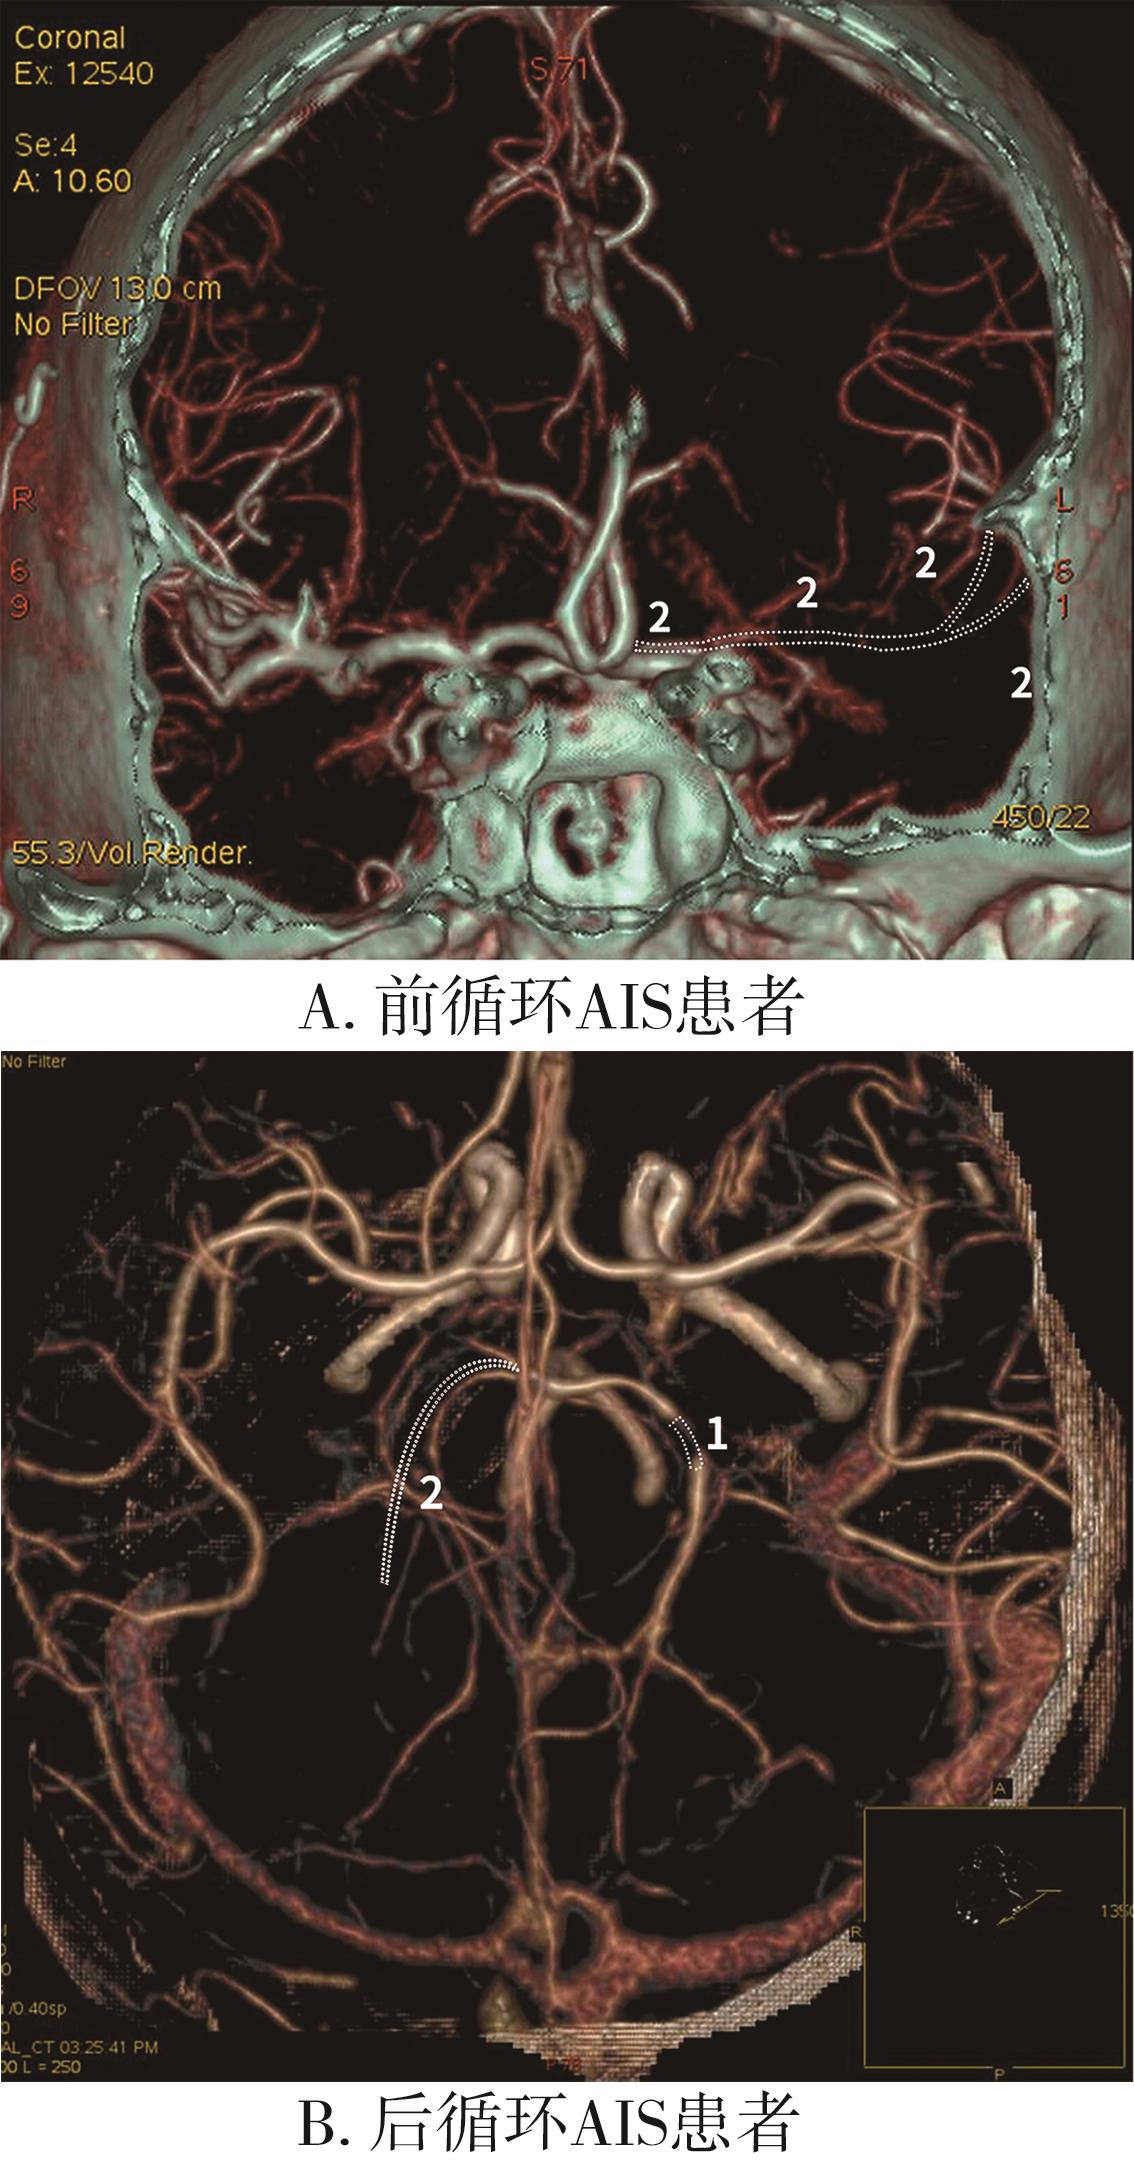

• 前后循环梗死评分系统:1种评估急性缺血性卒中患者预后的新方法

2024, 49(2):217-221. DOI: 10.13406/j.cnki.cyxb.003427

摘要 (46) HTML (38) PDF 1.32 M (77) 评论 (0) 收藏

摘要:目的 开发并验证一种新型急性缺血性脑卒中(acute ischemic stroke,AIS)评分系统-前后循环梗死评分系统(anterior and posterior circulation infarction image score,APCIIS)。方法 回顾性分析2020年6月至2021年6月在重庆医科大学附属第一医院收治的163例急性缺血性卒中患者的临床资料。将患者分为前循环AIS组(n=109)及后循环AIS组(n=54)。利用单因素和多因素分析影响前循环AIS及后循环AIS患者预后情况的危险因素。以血栓负荷评分(the clot burden score,CBS)及基底动脉闭塞评分(the basilar artery on computed tomography angiography score,BATMAN)为参考,绘制受试者工作特征曲线,分析该新型评分(APCIIS)预后评估的价值。结果 在前循环AIS组,APCIIS的预后评估价值虽然未能优于CBS,但显示出相对更高的敏感度86.8%、特异度90.1%及曲线下面积0.939。在后循环AIS组,APCIIS的预后价值优于BATMAN评分。结论 APCIIS是预测急性缺血性脑卒中患者预后的1种方便可靠的办法。

• 0+1

• 1+1

• 2+1

• 3+1